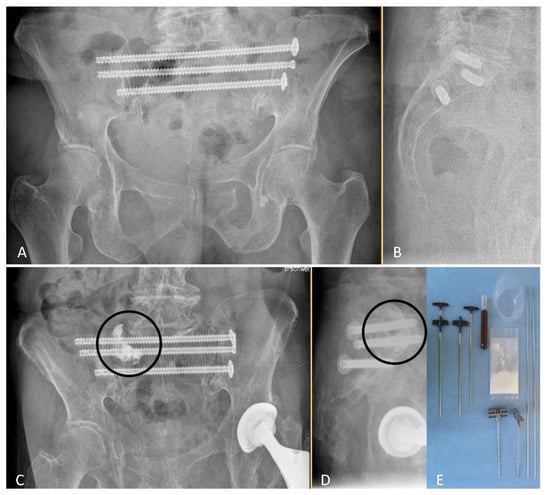

From October 2011 to May 2017, 52 individuals with 124 non-displaced sacral fractures had undergone surgery in form of NSF or NSF + ASP (Figure 1) after allocation to study groups.

Figure 1. Post-surgical radiographs (anteroposterior (A,C) and lateral views (B,D) in standing position) after NSF (A,B), or NSF + ASP ((C,D), cement location indicated by circles). Required disposable materials for an ASP procedure are shown in (E). NSF indicates navigation-assisted screw fixation; ASP, additional sacroplasty.